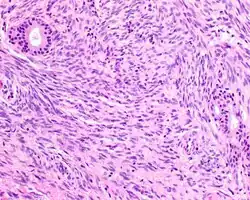

Hematoxylin and eosin stained image of a biphenotypic sinonasal sarcoma

• Infiltrative, highly cellular spindled cell neoplasm is poorly circumscribed and unencapsulated. Bone destruction or invasion is common. The cells show medium to long fascicles (nerve fibers), with a herringbone pattern. The cells are remarkably uniform with elongated nuclei. Delicate strands of intercellular collagen without ropy or dense deposition are seen. A very characteristic concurrent surface-type respiratory epithelial proliferation is found from the surface or in small cystic spaces around the cancer cells, often forming glands. The background may have a rich vascularity and usually has a small number of scattered lymphocytes. Extra growths or mitoses are rare, while necrosis, ulceration, and hemorrhage are usually absent.